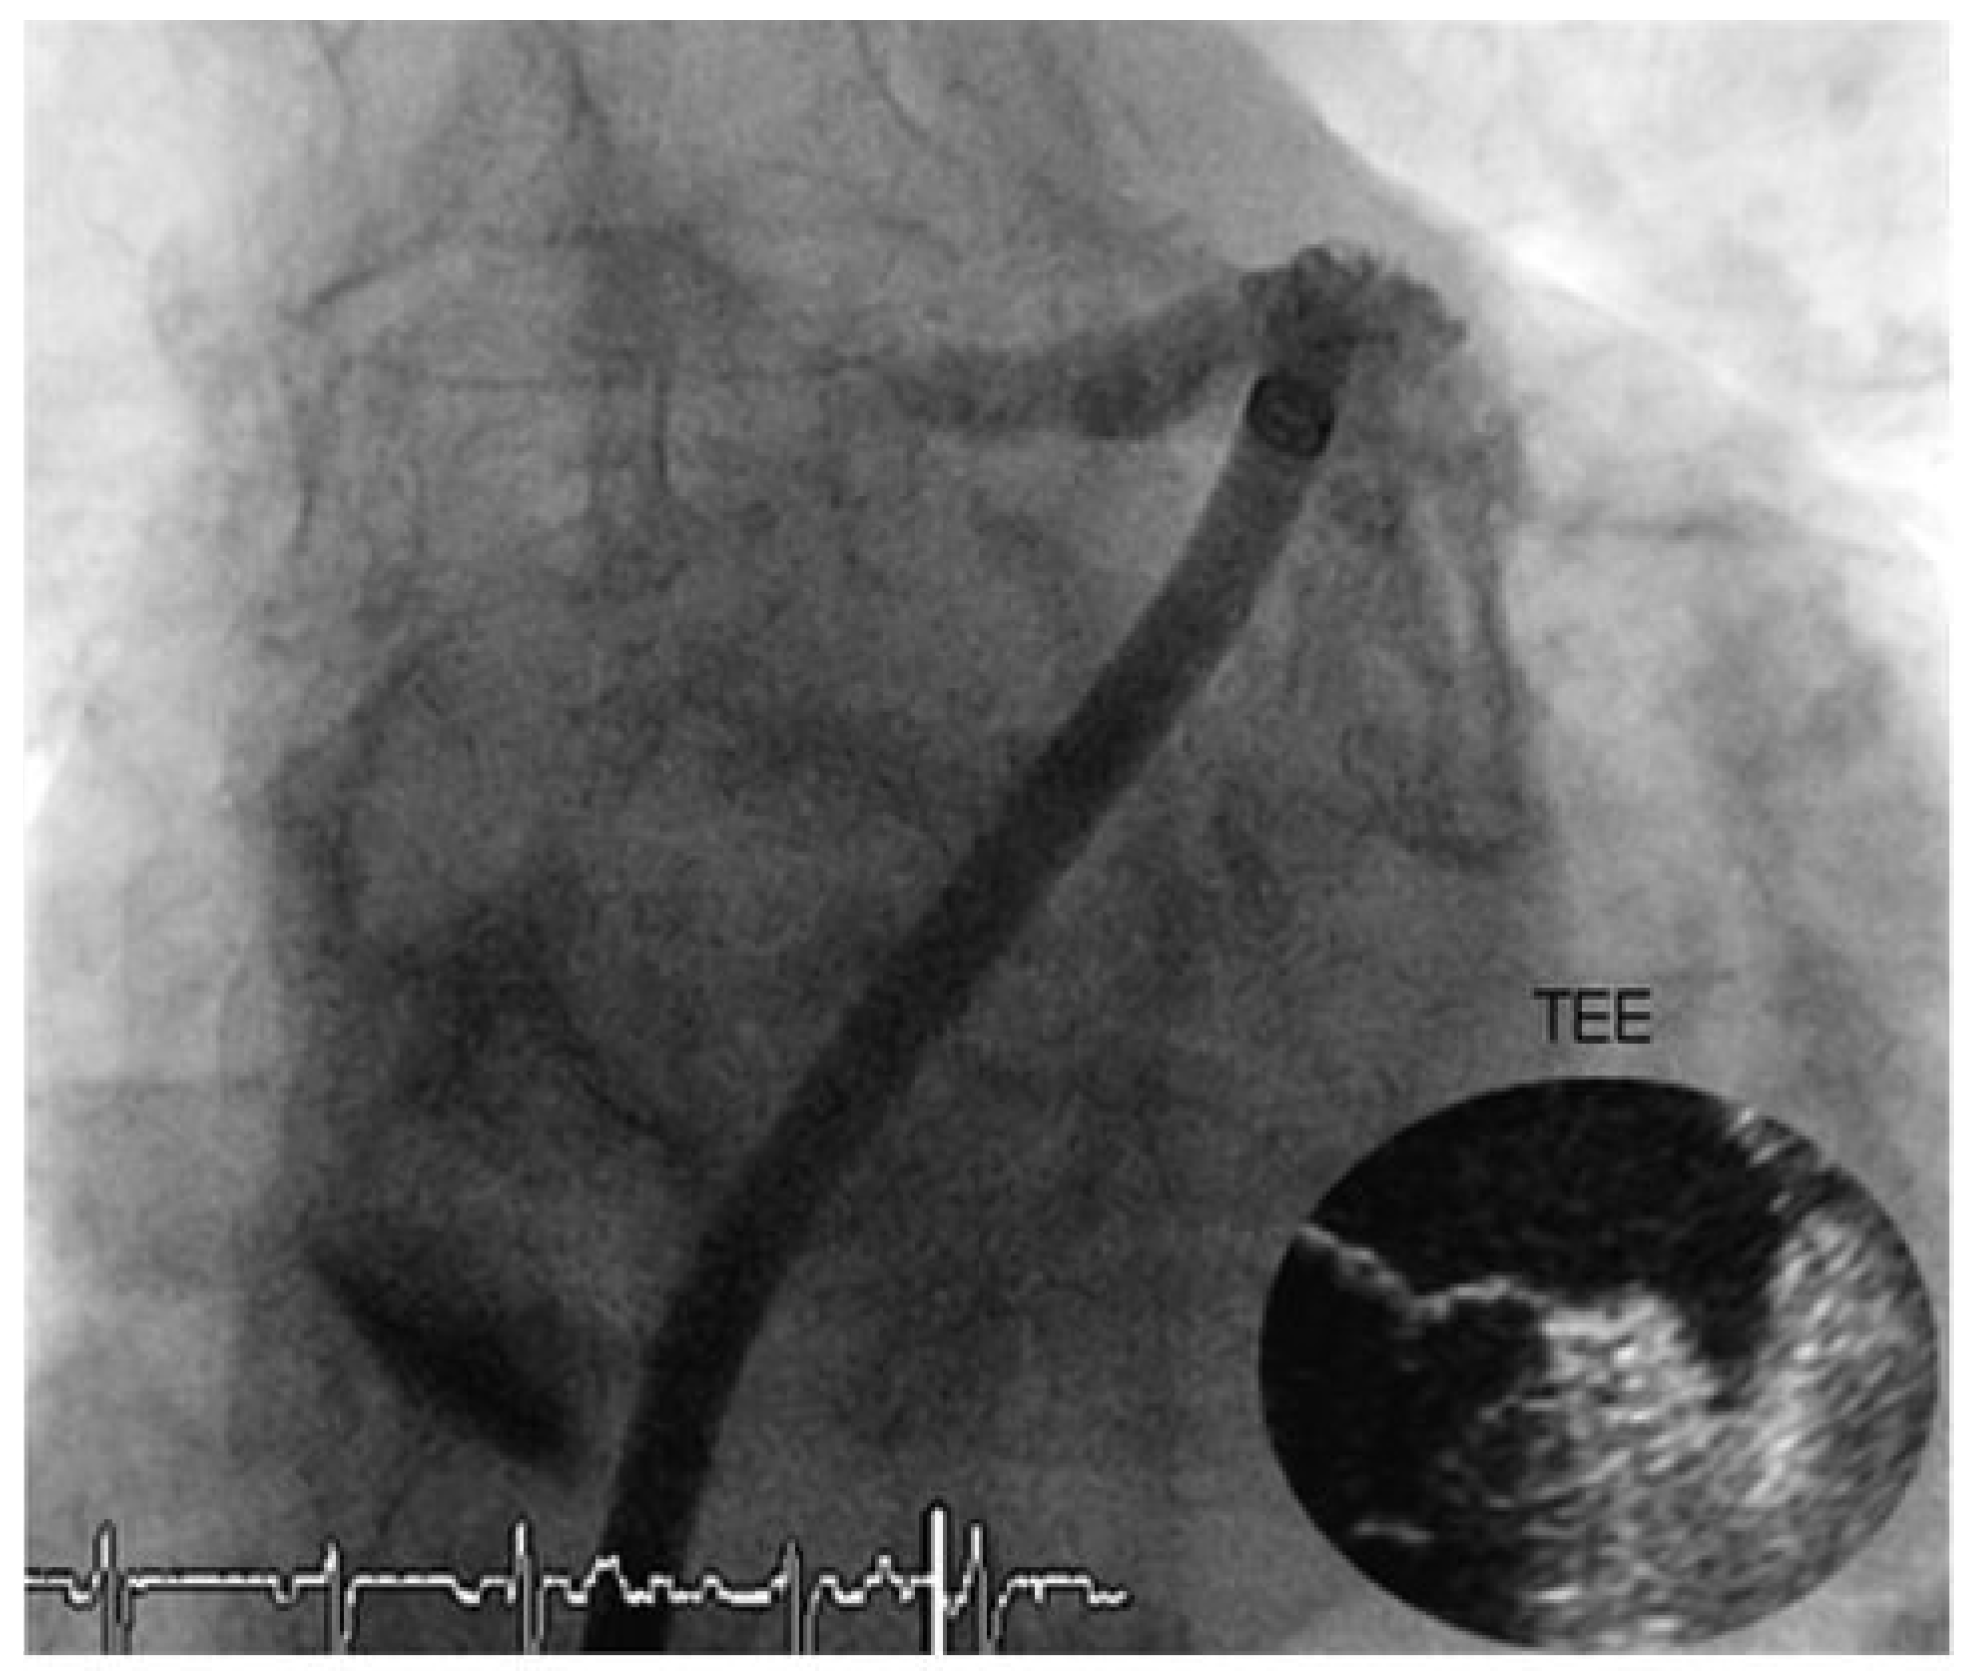

Through a transfemoral venous approach and transseptal puncture, the left atrial appendage was identified and an Amplatzer cardiac Plug 20 mm was positioned in the entry of the appendage. A stable position of the device and complete occlusion of the retroverted, single-lobulated appendage were verified by angiography before the device was released from the catheter (Figure 1 and Figure 2). Thereafter, coronary angiography was performed which showed significant stenosis of the mid left anterior descending coronary artery (LAD) and the proximal left circumflex coronary artery (LCX). Following successful treatment with two everolimus-eluting stents, respectively (Figure 3), angiography of the aorta and iliac artery was performed to measure the aortic valvar annulus and assess the peripheral access site. The patient qualified for implantation of a Medtronic CoreValve bioprosthesis and a 18 French sheath was introduced in the right femoral artery, as well as a temporary transvenous pacemaker through a right jugular access. After balloon dilatation of the degenerative aortic valve with a Nucleus balloon 25 × 40 mm under rapid pacing, the self-expandable bioprosthesis was deployed under fluoroscopic guidance (Figure 4). Periinterventional transoesophageal echocardiography demonstrated an excellent result with negligible paravalvular regurgitation. Simultaneous invasive measurement demonstrated a decrease in the mean transvalvular pressure gradient from 56 to 5 mm Hg. Closure of the right femoral access site was performed under temporary balloon occlusion of the right external iliac artery, from a contralateral femoral access with a Prostar device. The intervention was performed under general anaesthesia.

Figure 1. Left atrial appendage on cardiac catheterisation and transoesophageal echocardiography.